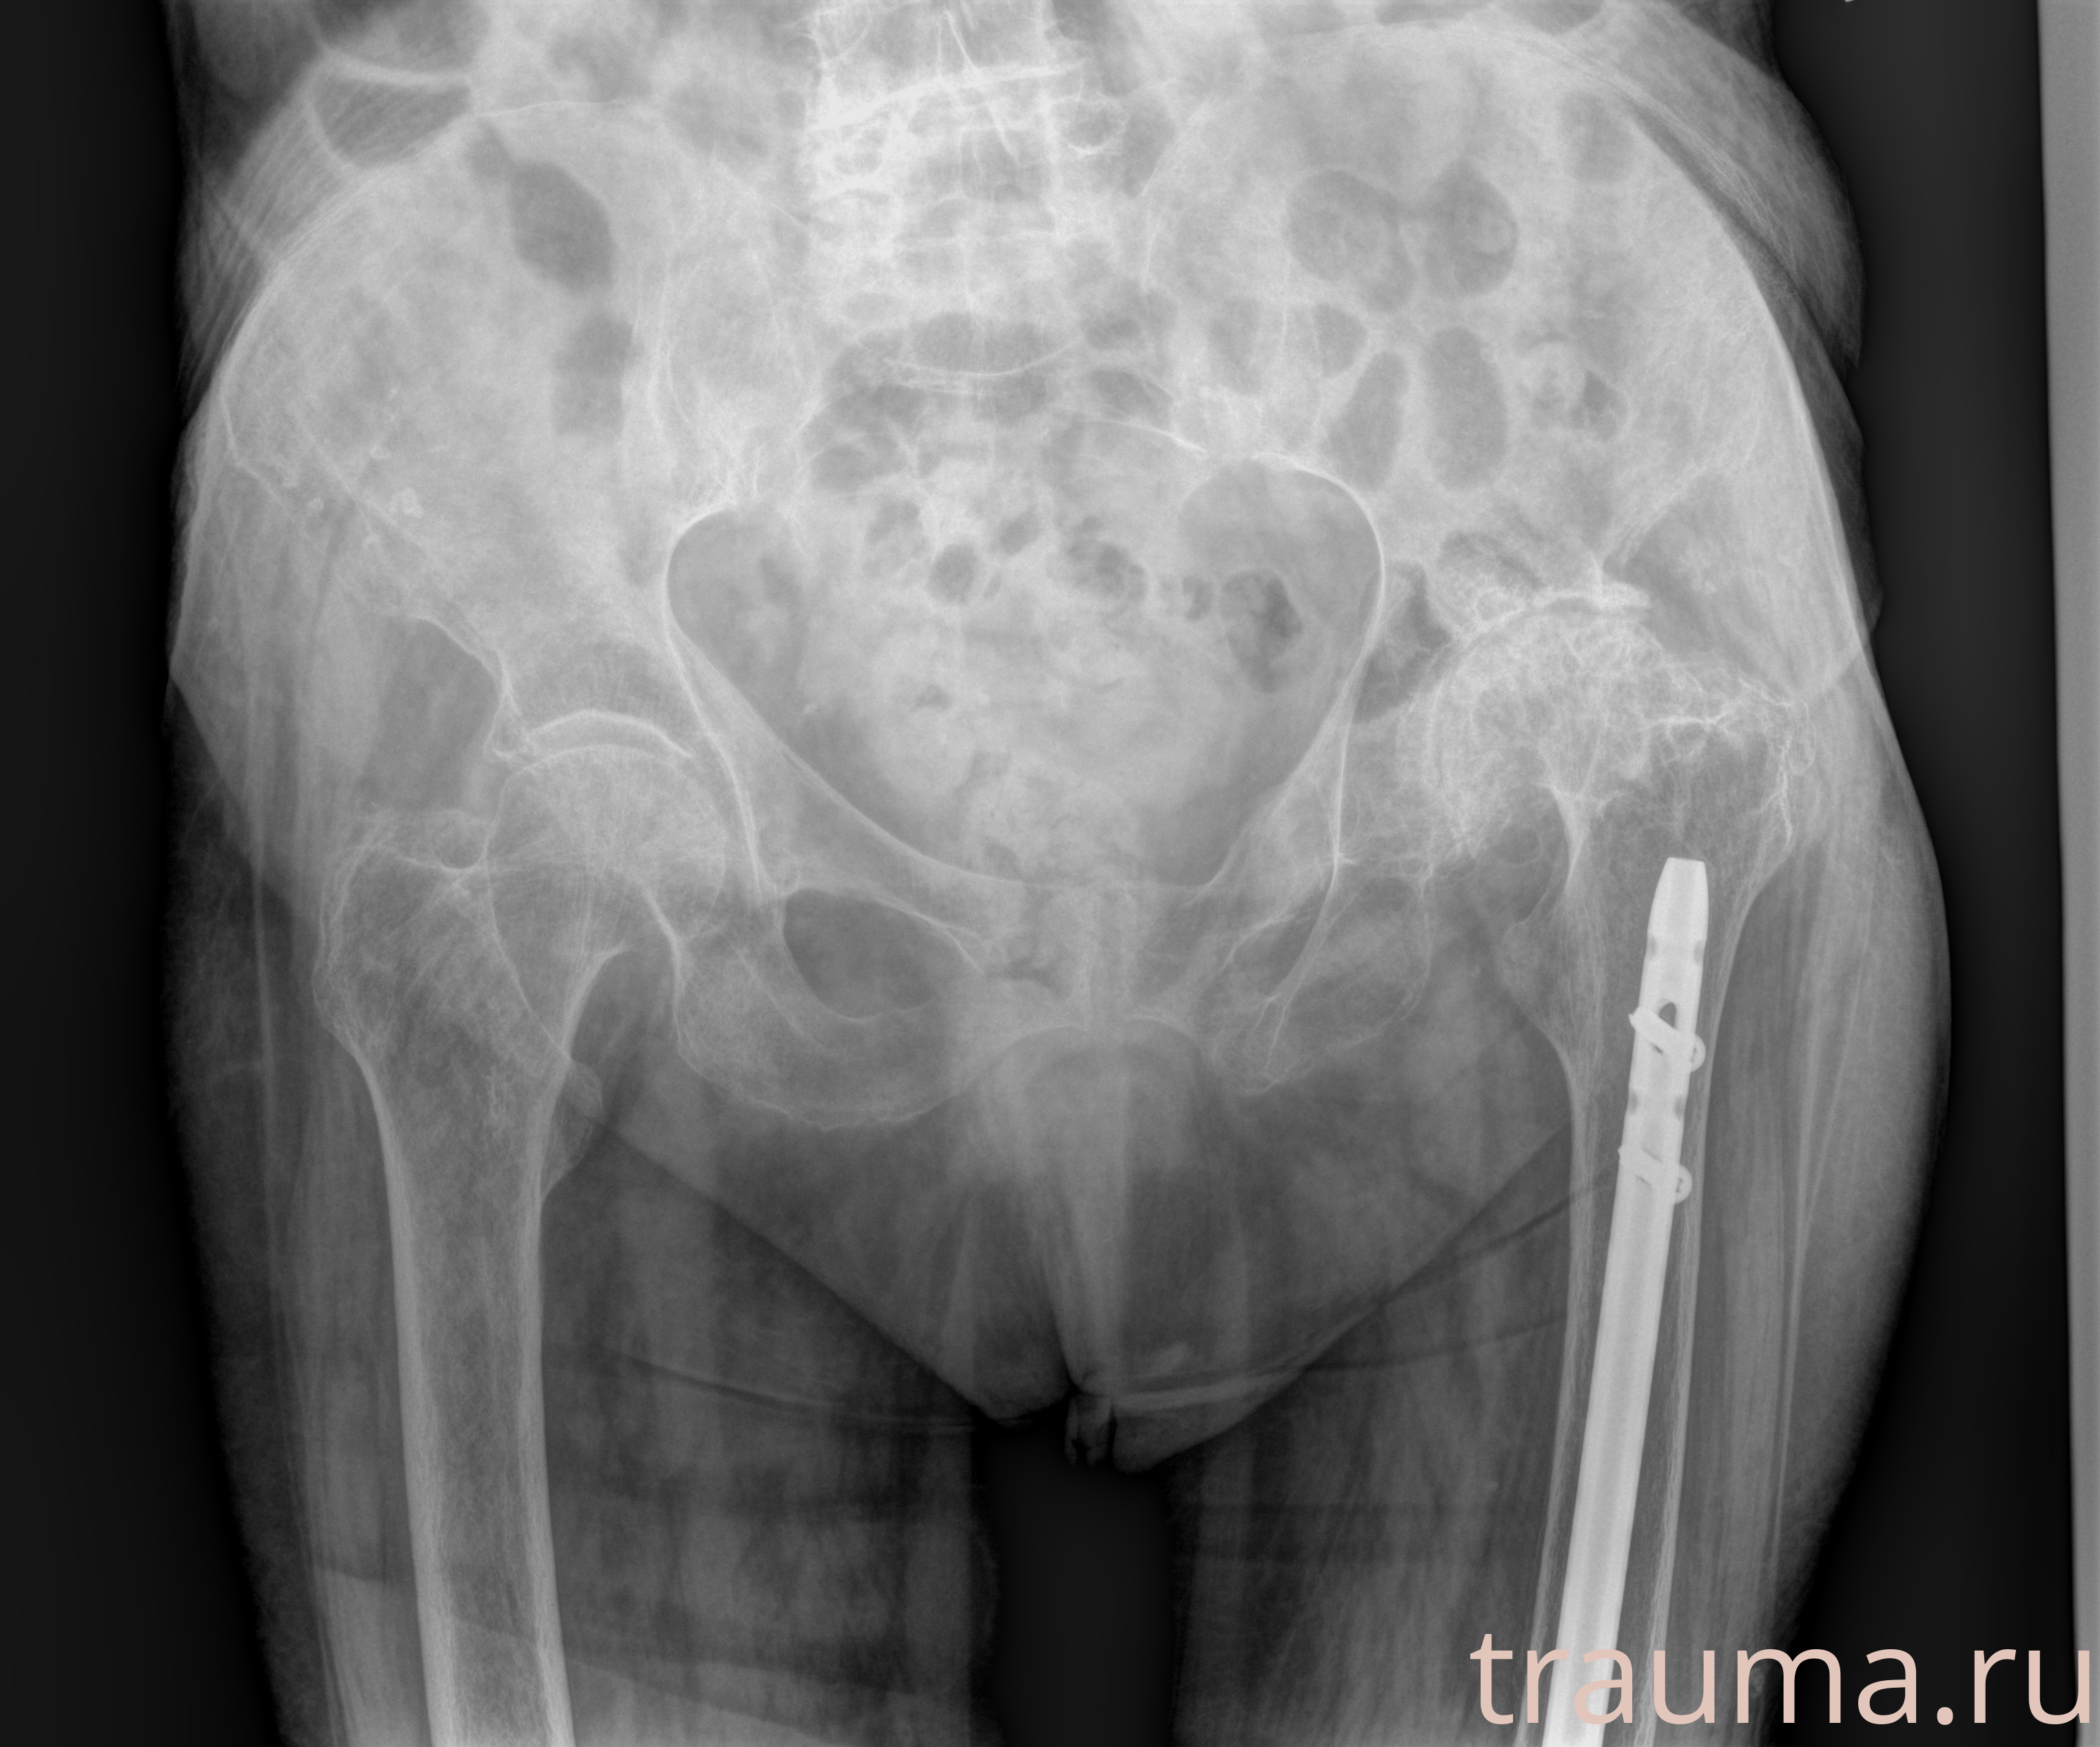

Перелом 3-5 ребер слева

Рентген на дому: по вашему адресу приезжает врач-рентгенолог, травматолог-ортопед с мобильным рентгеновским аппаратом, проводит диагностику травмы или заболевания, делает необходимые рентгенограммы, дает рекомендации по дальнейшему лечению. Получить качественные снимки в домашних условиях возможно благодаря уникальной методике, разработанной МосРентген Центром для института  Склифосовского

при переломе шейки бедра и пневмонии от компании МосРентген Центр - партнера Института имени Склифосовского